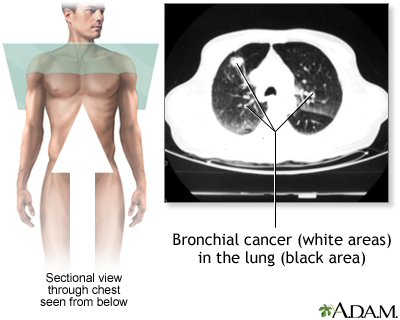

A chest CT (computed tomography) scan is an imaging method that uses x-rays to create cross-sectional pictures of the chest and upper abdomen.

- Lung cancer or cancer that has spread to the lungs from elsewhere in the body